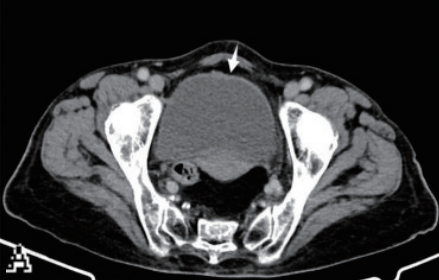

基础信息:患者男,42岁,尿血吸虫虫卵阳性,血清抗体1∶128,尿常规微量红细胞,无明显症状;采用通用泌尿系CT平扫(肾脏至耻骨联合,120kV/150mA,无延迟期,膀胱未充盈)。

影像表现与漏诊原因:双肾大小形态正常、密度均匀,平扫难辨早期间质炎症及肾功能异常;双侧输尿管无扩张增厚,5 mm层厚遗漏黏膜细微病变;膀胱半充盈、黏膜欠光滑,未充盈掩盖早期黏膜增厚,平扫无法识别炎症(图1)。

病情进展:半年后右侧腰痛,复查CT平扫示右肾盂重度扩张、肾实质变薄,右侧输尿管下段增厚狭窄、钙化,膀胱壁钙化,系早期漏诊延误干预。

图1

A:5 mm层厚泌尿系CT平扫冠状位示双肾大小形态正常、密度均匀,双侧输尿管无扩张增厚;

B:5 mm层厚泌尿系CT平扫轴位示膀胱半充盈、黏膜欠光滑